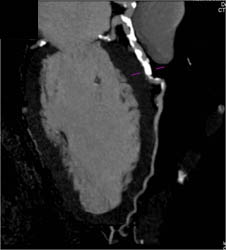

Normal Ramus Intermedius